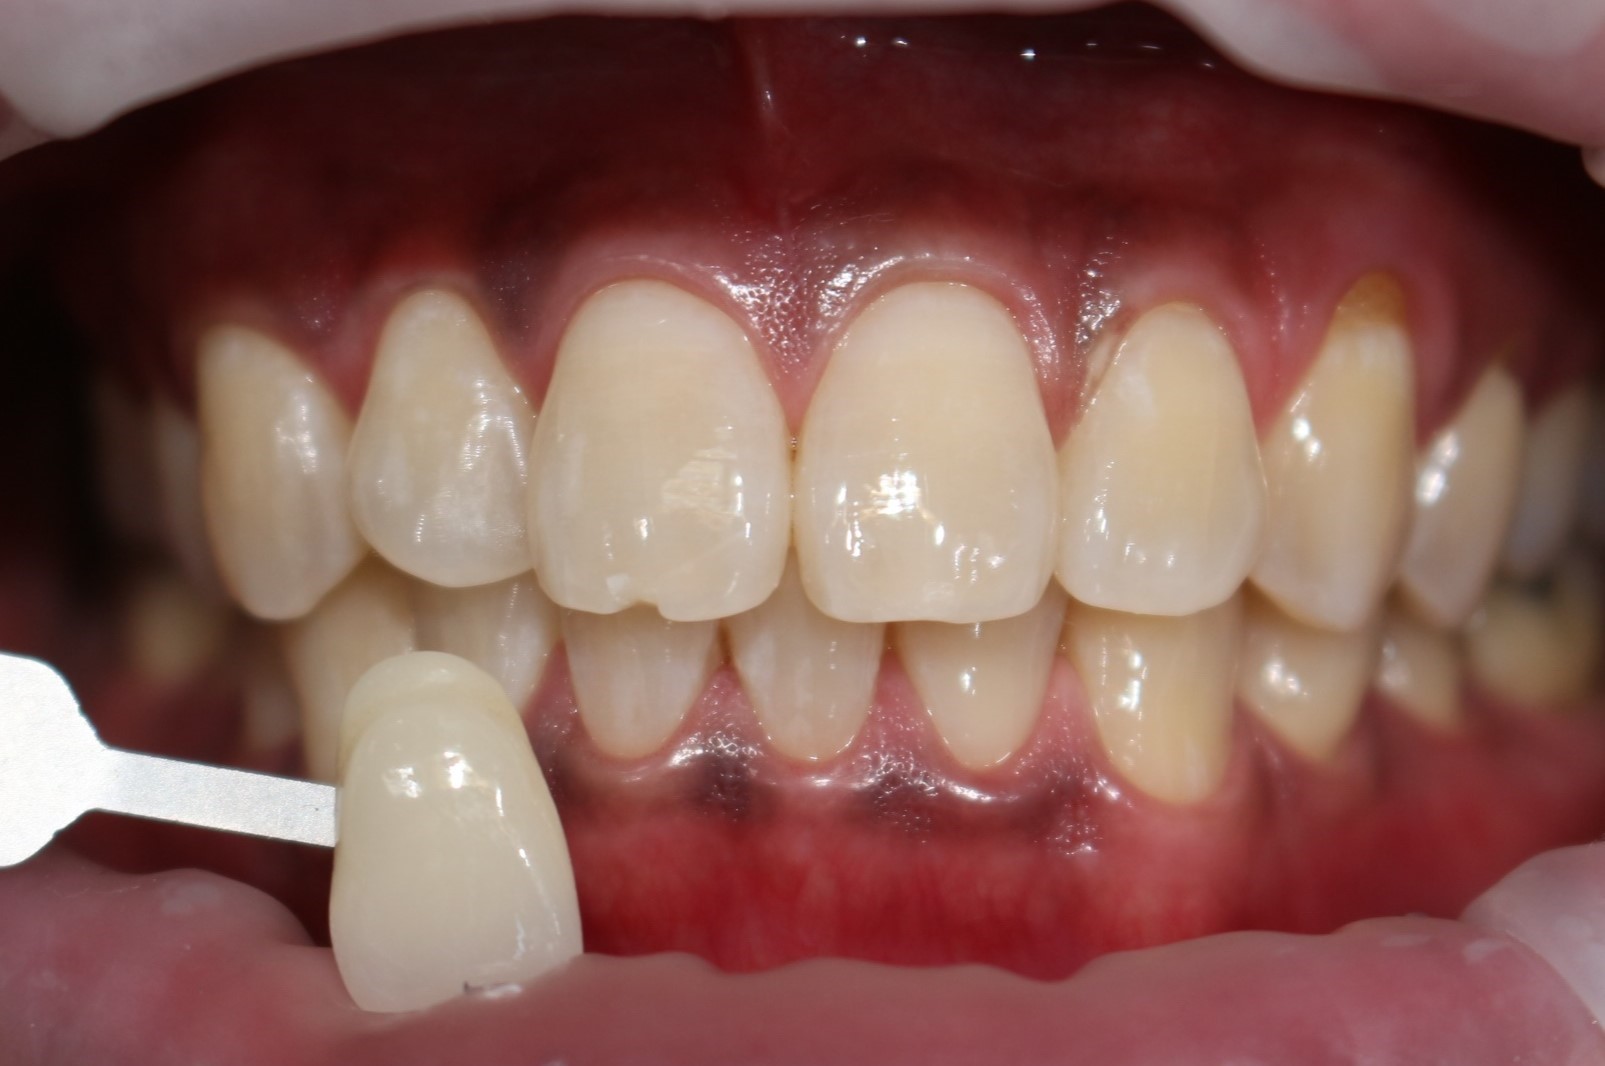

수술 전

수술 후

원데이 치아미백

전후사진